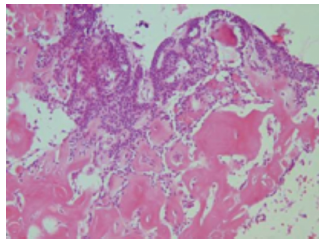

In 5 patients, the frozen section was only able to determine the tumor grade, and the type of tumor was contingent on full pathologic examination with sample staining. Of these 5 patients, 1 had a high-grade tumor and 4 had a low-grade lesion. Organ donation was not performed for the patient with the high-grade tumor. In the other 4, organ donation was performed after the final pathology report was received. In 3 frozen-section reports, the type of tumor was diagnosed accurately: these included 1 medulloblastoma (Figure 1), 1 meningioma, and 1 patient with a subarachnoid hemorrhage but no tumor. The final pathology report for the 5 patients that only received a grade during frozen section was meningioma in 1 patient, craniopharyngioma in 1 patient (Figure 2), astrocytoma in 2 patients, and neurofibroma in 1 patient.

Figure 1. Medulloblastoma

Figure 2. Craniopharyngioma